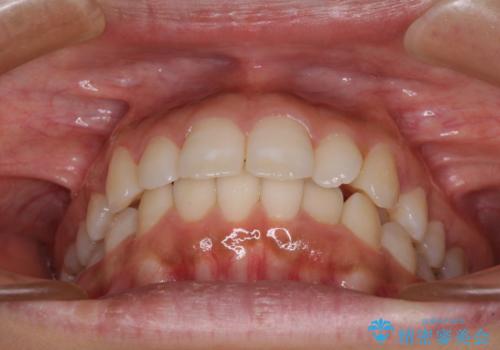

- 出っ歯で唇が閉じにくいとのことで来院された患者様です。

顎先に力を入れないと唇が閉じきれない口元であったので、上下左右の第一小臼歯4本を抜歯して、ワイヤー装置にて矯正治療を行うこととしました。

2年から2年半の治療期間を想定しており、予定通りの期間で無事に終了することができました。

唇や顎先に力を入れないなくてもスムーズに唇を閉じることができるようになりました。